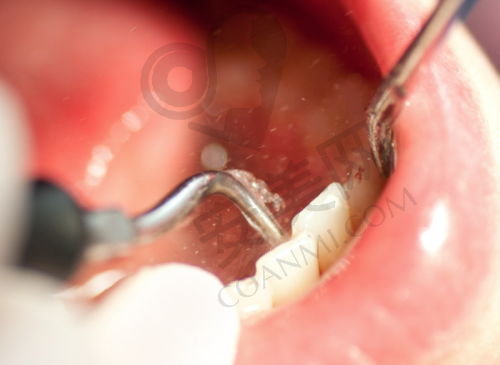

确定好治疗方案后,就开始了第一次治疗。医生先给我进行了局部麻醉,在打麻药的时候,稍微有一点刺痛感,但特别快就过去了。麻醉起效后,医生用专精的牙科工具在我的牙齿上开了一个小孔,这个过程我基本没有感觉到疼痛。开髓的目的是为了引流牙齿内部的炎症渗出物,缓解牙齿的压力,从而减轻疼痛。之后,医生在牙齿里放了一个棉球,让我先回家观察几天。在回家后的几天里,牙齿的疼痛明显减轻了。